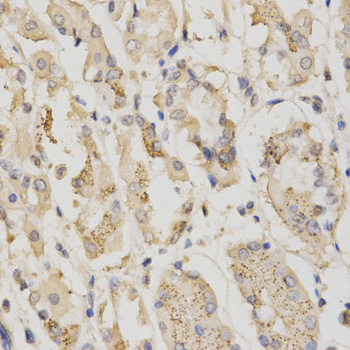

Immunohistochemistry of paraffin-embedded human stomach using STK11 antibody at dilution of 1:200 (x400 lens)